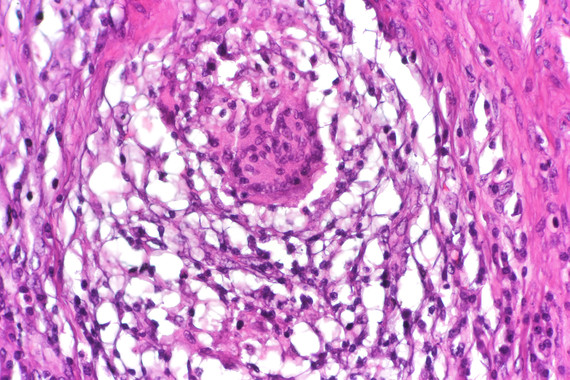

Un fármaco para tratar las fístulas de Crohn con células madre de donantes

Agencia SINC Un equipo científico español ha presentado hoy en Madrid un fármaco pionero, basado en una tecnología del CSIC con células madre de donantes, para tratar las fístulas de la enfermedad de Crohn. El medicamento se basa también en otras patentes de grupos españoles, entre ellos, la Universidad Autónoma de Madrid (UAM), y trata […]